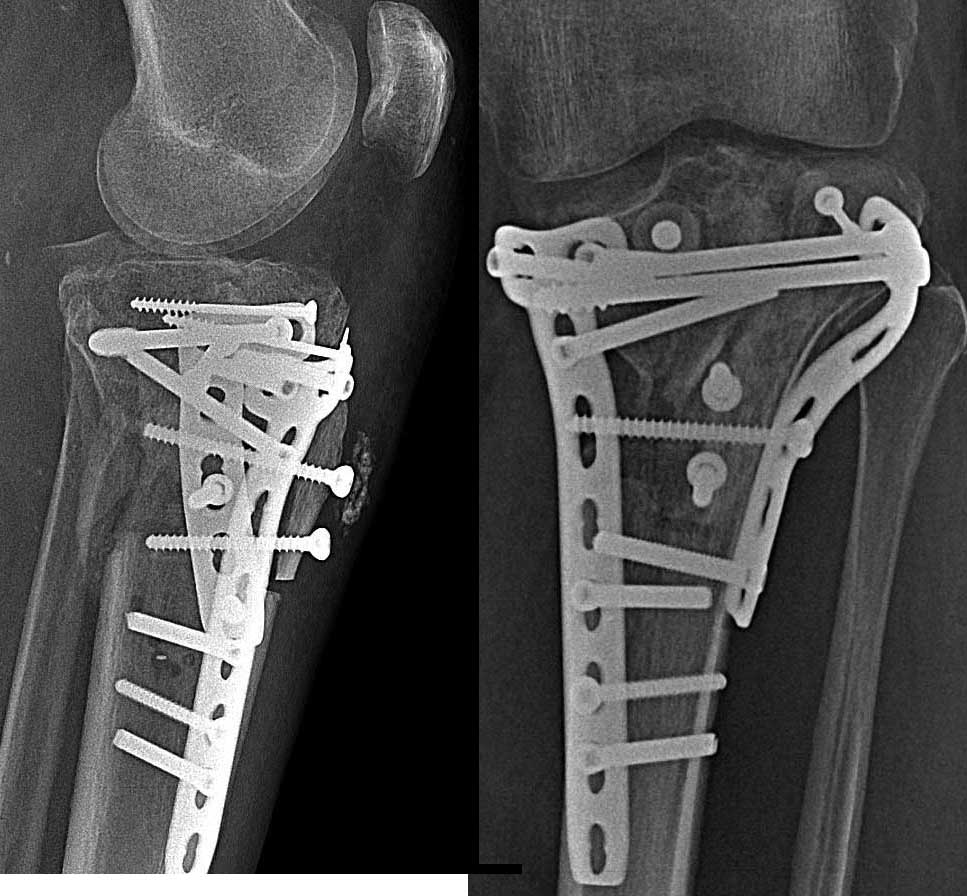

|  После операции |  Через 4 мес. |  После удаления | Травма бытовая от 14.08.13 – падение с высоты 2х метров, на полусогнутую левую ногу. Доставлен бригадой СМП в травмпункт, шинирован. В травипункте обследован клиничеки и рентгенологически – закрытый оскольчатый перелом внутреннего мыщелка левой большеберцовой кости со смещением и подвывихом голени кнаружи. Обезболен, наложена гипсовая шина. Направлен на стационарное лечение. При поступлении – ССВ за пяточную кость. Дообследован. 20.08.13 – остеосинтез большеберцовой кости пластинами LCP и винтами. Послеоперационное течение без особенностей. Заживление ран первично. 06.09.13 – выписан на амбулаторное долечивание с рекомендациями. В травмпункте – динамическое наблюдение. Ходьба 3 месяца без нагрузки на левую ногу. Фиксация жестким ортезом. В процессе реабилитации – контрактура сустава (разработанна), комбинированная нестабильность левого коленного сустава. Рентгенограммы в динамике – проседание отломков внутреннего мыщелка. 06.11.13 консультирован областным ортопедом - неправильно консолидирующийся перелом мыщелков левой большеберцовой кости. Genu Varum. Несостоятельность НБС, ПКС. Рекомендовано – фиксация ортезом, доведение нагрузки до полной. Через месяц решение вопроса об удалении металлоконструкции и пластика связок. В процессе реабилитации динамика слабоположительная. Дообследован. 15.01.14 – удаление металлоконструкции с левой большеберцовой кости. Послеоперационное течение относительно гладкое. Долечивание в травмпункте. ФТЛ. Ходьба с дозированной нагрузкой. Объективный статус: общее состояние удовлетворительное, сознание ясное, кожный покров физиологической окраски, периферические лимфоузлы не пальпируются. В лёгких дыхание везикулярное по всем полям, хрипов нет. Тоны сердца ясные, ритмичные, АД 140 и 90 мм .рт. ст. Ps 95 в 1 мин. Живот мягкий, безболезненный, печень по краю рёберной дуги, почки не пальпируются, Нарушения тазовых органов нет.

Локально: Стойкий болевой синдром при нагрузке и движениях в левом коленном суставе. Ходит на костылях с незначительной нагрузкой на ногу. При передвижениях использует жесткий ортез. Кожа левого коленного сустава физиологической окраски. Отек незначительный, контуры левого сустава сглажены по сравнению с правым. Выпота всуставе нет. Послеоперационные рубцы в\3 левой голени, без признаков воспаления. Положительные тесты «переднего выдвижного ящика», «Pivot shift», «Jerk». Неврологических и ангиотрофических расстройств дистальней нет. Рентгенографическое обследование в динамике прилагаю. КТ, МРТ - нет.

Внутренний мыщелок нерепонирован изначально.

Резюме: сначала восстановите анатомию костных структур. Возможно ли? - не на 100%, так как есть невосполнимые потери собственно суставной поверхности. Метафизарные дефекты требуют костной пластики больше с точки зрения биологической поддержки, чем механической. Метафиз после удаления пластин выглядит "измученным" и не очень здоровым.

связки на таком варусе сложно оценить. Для определения дальнейшей тактики без СТ не обойтись, не очень понятен фрагмент сзади. А так, реоперация - элевация внутреннего мыщелка с костной пластикой и опорной пластиной

О типичных ошибках в лечении переломов тибиал плато по Schatzker IV я говорил во всех прежних выступлениях. Не было нужды фиксировать интактную латеральную колонну пластиной, потому что удержать медиальную колонну без фиксации медиального мыщелка невозможно. Пластина даже с угловой стабильностью не удержит от варусных сил!

Все внимание на медиальной стороне, и здесь кроме фиксации перелома медиального мыщелка надо подумать как восстановить типичное смещение кзади. Одна медиальная пластина не может предотвратить скольжение, потому что винты находятся в другой плоскости. Через медиальный фрагмент прошли минимум винтов и не создан противоскользящий эффект мыщелка задней пластиной.

Не восстановлен дефект кости, а дефицит привел к несращению. Костная пластика метафизарных отделов, кроме биологии, создает структуральную подержку, иначе быстро уходит в коллапс.

Надо сделать сравнительные снимки конечности больших размеров и КТ. Цель операции - создание конгруентности сустава на одном уровне. 3Д позволит увидеть смещение и остеотомия медиального мыщелка с разворотом будет достаточным, чтобы уйти от варуса. Одна или две пластины в зависимости от достигнутой коррекции, а для дефекта графт. Временный наружный фиксатор (аппарат Илизарова) для профилактики варуса.